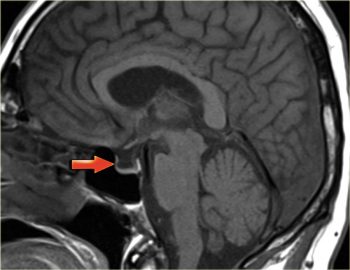

Синдром пустого турецкого седла причины симптомы лечение